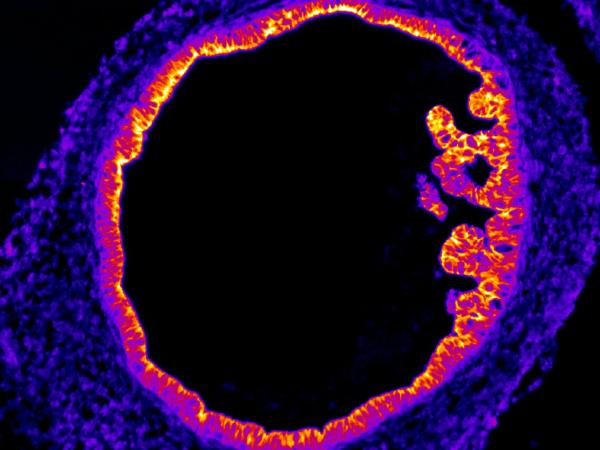

HIO/Intestin ©MMahé Blastocyste ©LDavid Mésothélium ©CBlanquart Rhéomètre ©PF Bio3

Organoids are cellular models that are an intermediate step between monolayer cell cultures and in vivo models. They have been developed thanks to advances in stem cell culture and differentiation, as well as 3D culture, over the last few decades. These three-dimensional models have the advantage of being produced from cells of the same species, unlike animal models. Using them therefore makes it possible to replicate physiological and/or pathophysiological conditions more closely, thereby increasing our knowledge of tissue function in the presence or absence of external molecules.